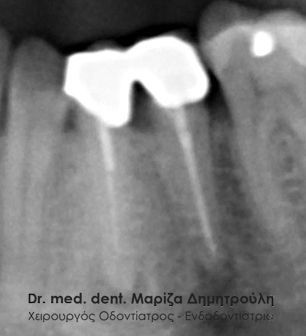

Στο συγκεκριμένο περιστατικό η μορφολογία της ρίζας παρουσιάζει ιδιαίτερο ενδιαφέρον, καθώς η ρίζα έχει τη μορφή τελικού “S”. Απουσιάζει η αρχική ακτινογραφία του δοντιού. Η απονεύρωση διεκπεραιώθηκε χωρίς να θιγεί η ανατομία της ρίζας του δοντιού.

Περιστατικό – Aπονεύρωση δοντιού

Στο συγκεκριμένο περιστατικό απουσιάζει η αρχική ακτινογραφία. Στην τελική ακτινογραφία φαίνεται η ομοιόμορφη συμπαγής έμφραξη των ριζικών σωλήνων των δοντιών. Επίσης το υλικό απονεύρωσης καλύπτει όλο το μήκος των ριζών του δοντιού, κάτι που είναι σημαντικό για την πρόγνωση του δοντιού.